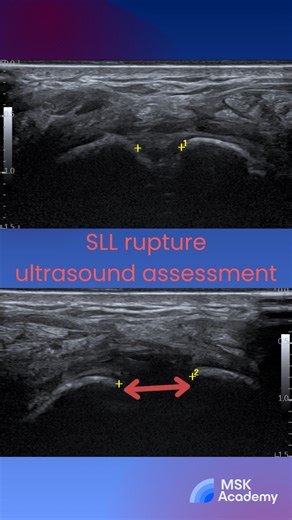

MSK Australia on Instagram: "🖐️ Scapholunate ligament on ultrasound Focus on the dorsal scapholunate ligament - the strongest and most clinically important component. Using a high-frequency linear probe over the dorsal wrist, a normal ligament appears as a continuous fibrillar band between the scaphoid and lunate. ⚠️ Tear signs: loss of fibrillar pattern, hypoechoic gap, or widening of the scapholunate interval, often more evident on dynamic scanning. Dorsal ligament disruption is the key drive